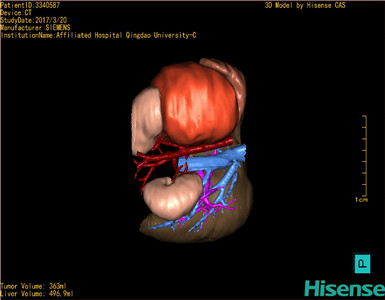

术前三维重建及手术方案设计:

将0.625mm双源薄层CT资料的静脉期和动脉期Dicom格式文件导入海信CAS系统。

通过调节窗宽窗位调整CT序号,对肿瘤,肝实质,胆囊,下腔静脉,肿瘤,肝动脉、门静脉及肝静脉等进行三维重建;系统自动计算肿瘤体积和肝脏体积。

模拟手术操作,自动计算切除肿瘤体积。肝脏体积为496.9ml,肾上腺肿瘤体积363ml,术前规划手术方案,进行手术。

术前三维重建:

重建图片